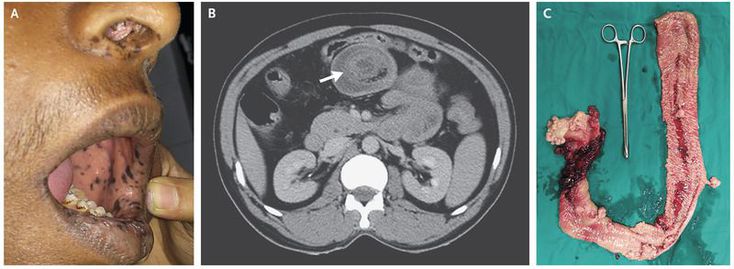

A 45-year-old man presented to the emergency department with sudden-onset abdominal pain and vomiting. On physical examination, his abdomen was diffusely tender, and he had hyperpigmented macules on the lips, oral mucosa, and nose (Panel A). His two sons had previously presented with abdominal pain due to intussusception and had undergone bowel resection. A computed tomographic scan of the patient’s abdomen showed a target sign (Panel B, arrow), which is characteristic of intussusception. Emergency laparotomy confirmed the presence of jejunojejunal intussusception with areas of necrosis. Multiple polyps were palpated throughout this section of the bowel. Because of the necrosis and concern about recurrence, the length of jejunum that contained polyps was resected (Panel C), and end-to-end anastomosis was performed. Histopathological evaluation of the resected segment revealed multiple hamartomatous polyps. On the basis of the mucocutaneous hyperpigmentation, multiple hamartomatous polyps in the gastrointestinal tract, and family history, a diagnosis of the Peutz–Jeghers syndrome was made. This autosomal dominant disorder is associated with an increased risk of gastrointestinal and extraintestinal cancers. The patient recovered well after the surgery and has undergone appropriate cancer-screening tests, which have been negative to date.